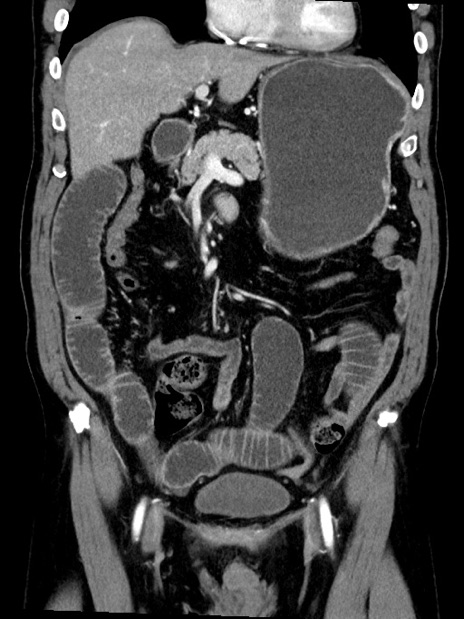

症例35(冠状断像)

【症例】70歳代 男性

【主訴】腹部膨満、嘔吐

【現病歴】昨日より腹部膨満感出現。本日増悪し、仙痛出現。嘔吐あり、受診。

【既往歴】糖尿病、胆摘後

【身体所見】BP 149/80mmHg、HR 74/min、BT 35.9℃、腹部:膨満、軟、圧痛なし。腸雑音減弱あり。上腹部正中切開瘢痕あり。

【データ】WBC 13500、CRP 1.72